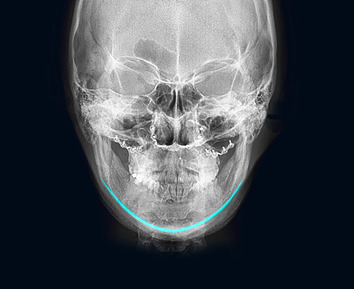

First of all, it is important to accurately analyze the shape of the cheekbones before surgery. It is necessary to consult with a clinician who has a lot of clinical experiences based on the results of X-ray and 3D-CT. At surgery, cheekbones are shaved based on the diagnosis. Depending on the skin elasticity of the person, an additional lifting procedure may also be recommended so the tissues are lifted together to give a lifting effect.

The facial bones do not grow after the growth period is over. In addition, cheekbone reduction surgery is a procedure in which the protruding cheekbone itself is moved inward and fixed to a new position, so you can rest assured that the cheekbones size will not increase again after surgery.

In case of cheekbone reduction surgery where your bone is completely cut, pins are needed to tightly fix the skin tissue and muscles and make them heal faster between the bones. This procedure equally happens with the other facial contouring surgeries too. Three months after the surgery, the bone is fully healed and firmly bonded as before the operation.